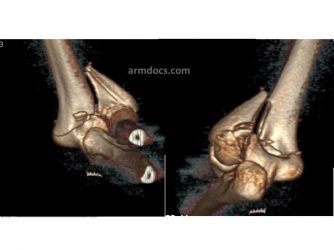

Fractures of the distal humerus may be suspected from the mechanism of injury resulting in pain, deformity and bruising over the outer aspect of the elbow. The diagnosis is confirmed on X-rays of the elbow. In most instances a CT scan will be arranged to study the fracture in greater detail and help plan surgical treatment.